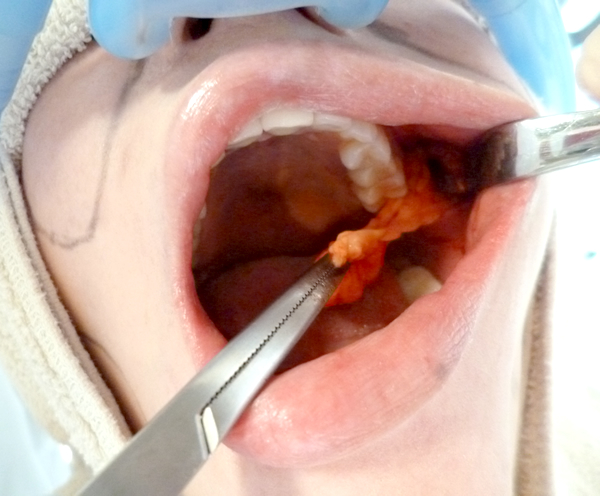

写真で見る「バッカルファットを除去する様子」

⑤ バッカルファット

の切除

⑥ 切除量の調整

切除後の脂肪(バッカルファット)